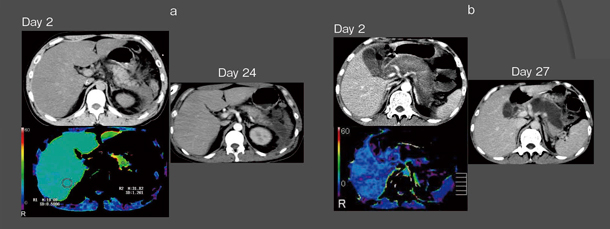

2007年に発表した論文1)では,発症3日以内の膵のPerfusion CTでは,壊死予測の感度は100%,特異度は95.3%と,非常に高いことがわかった。図2aの浮腫膵炎の例では,Day 2のPerfusion CTで膵臓の一部に血流が比較的あるように見えており,Day 24で壊死はしていない。図2bの例では,造影CTではDay 2での評価は難しく,淡く造影されているように見えるが,Perfusion解析では完全に血流は観察されず,すでに壊死していると判断できる。Day 27の造影CTで,Perfusion CTで観察された領域に一致して壊死が認められ,Perfusion CTによる壊死予測は非常に有用であることが確認された。

図2 Perfusion CTの有用性

発症早期のPerfusion CTによる壊死予測の感度は100%,特異度は95.3%であった。